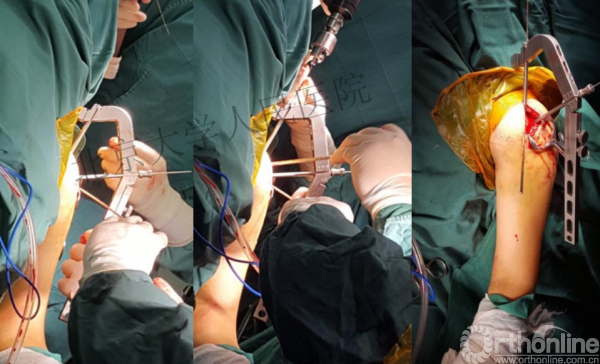

进钉更完美——我们的帮助

术中片